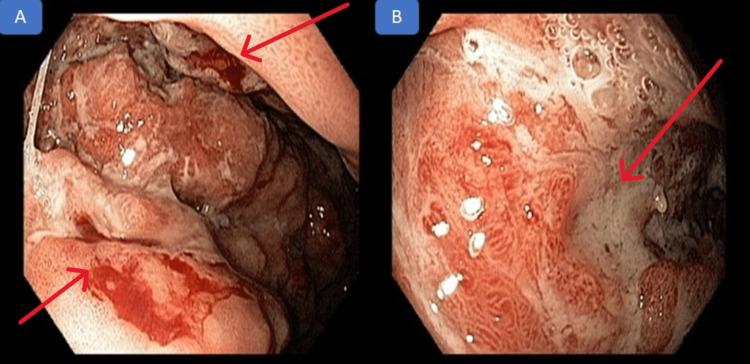

is a condition related to the extracellular deposition of abnormal fibrillar proteins. Gastric involvement may present as a systemic or localized form of the disease. The endoscopic presentation can vary from nodular, ulcerated, or infiltrative lesions. Clinical manifestations are nonspecific, including hyporexia, nausea, vomiting, weight loss, epigastralgia, and abdominal discomfort. Thus, amyloidosis can clinically and endoscopically mimic other diseases, such as neoplasms, syphilis, tuberculosis, and Crohn's disease, requiring a high suspicion. When it manifests with gastrointestinal bleeding, it most commonly occurs as intermittent melena. This report aims to present an unusual case of a patient with upper gastrointestinal bleeding exteriorized through melena secondary to amyloidosis with gastric involvement.

是一种与异常纤维状蛋白的细胞外沉积相关的病症。胃部受累可能表现为该疾病的全身性或局限性形式。内镜表现可从结节状、溃疡性或浸润性病变不等。临床表现无特异性,包括食欲减退、恶心、呕吐、体重减轻、上腹痛和腹部不适。因此,淀粉样变性在临床和内镜下可模仿其他疾病,如肿瘤、梅毒、结核病和克罗恩病,需要高度怀疑。当它表现为胃肠道出血时,最常见的是间歇性黑便。本报告旨在介绍一例不寻常的病例,该患者因淀粉样变性累及胃部,通过黑便出现上消化道出血。